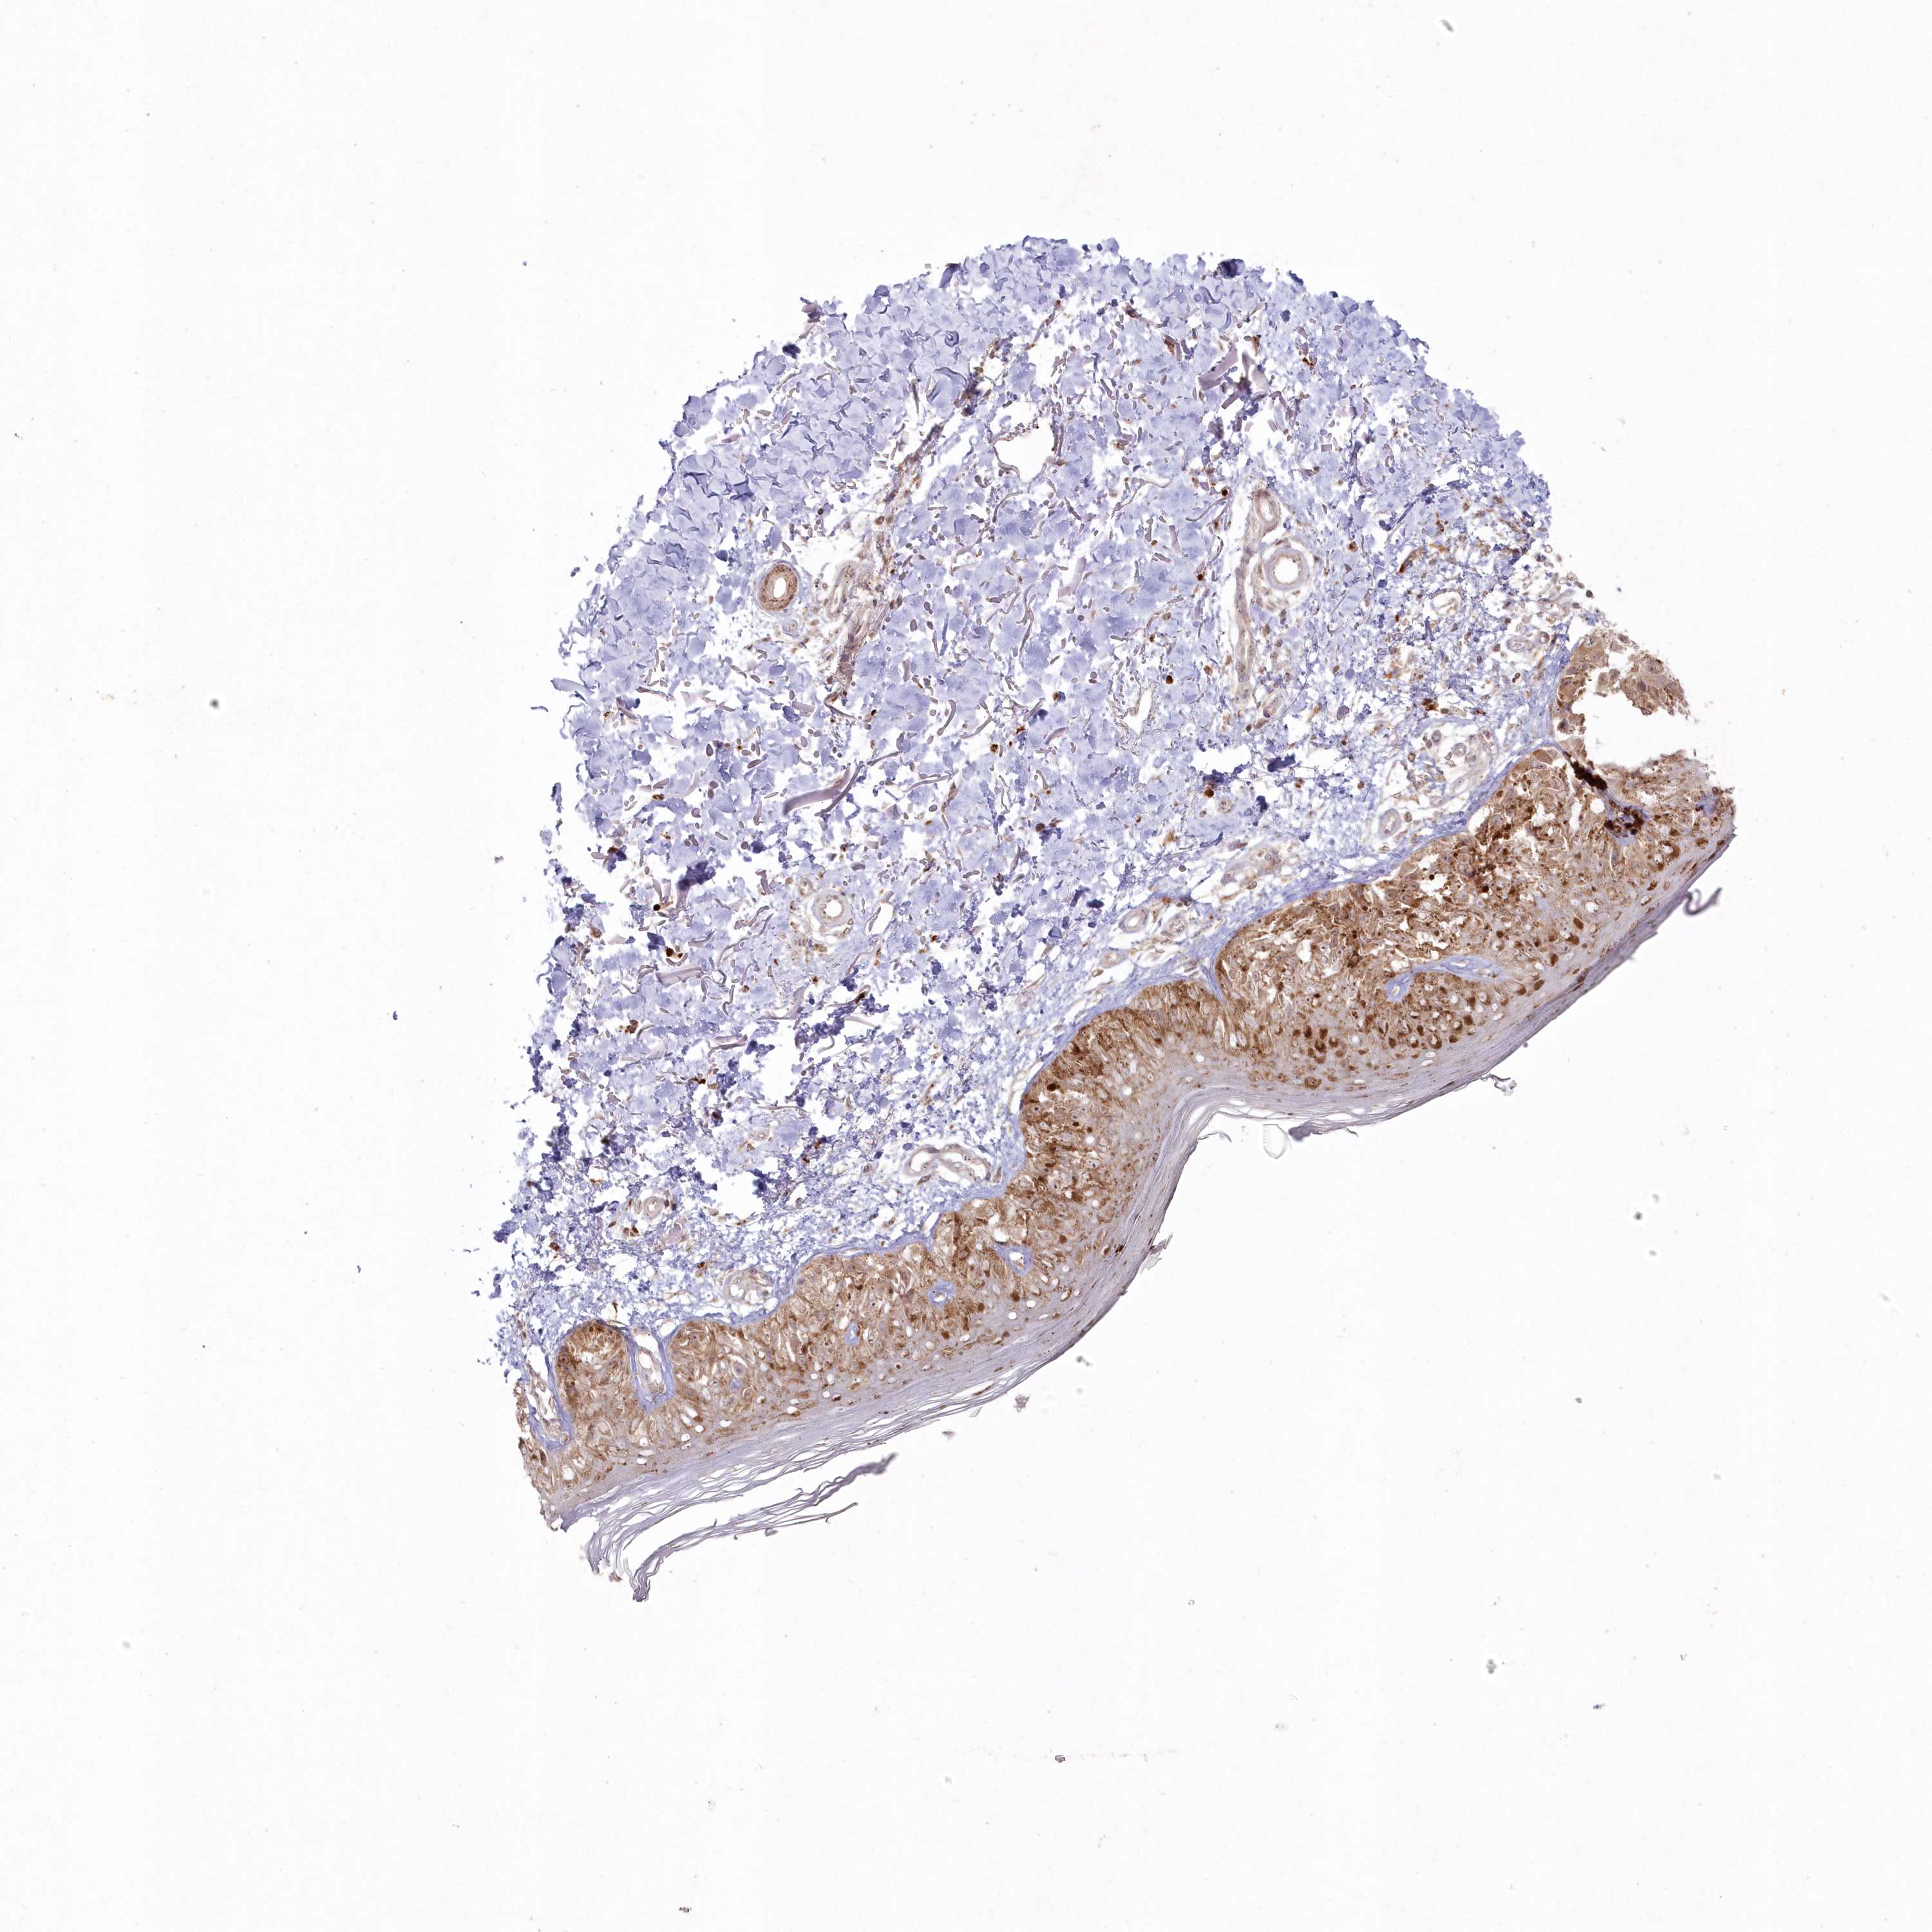

MELANOMA - Protein expressioni

A mouse-over function shows sample information and annotation data. Click on an image to view it in a full screen mode. Samples can be filtered based on level of antibody staining by selecting one or several of the following categories: high, medium, low and not detected. The assay and annotation is described here.

Note that samples used for immunohistochemistry by the Human Protein Atlas do not correspond to samples in the TCGA dataset.

Antibody stainingi

Antibody staining in the annotated cell types in the current human tissue is reported as not detected, low, medium, or high, based on conventional immunohistochemistry profiling in selected tissues. This score is based on the combination of the staining intensity and fraction of stained cells.

Each image is clickable and will lead to virtual microscopy that enables deeper exploration of all samples and also displays staining intensity scores, fraction scores and subcellular localization as well as patient and tissue information for each sample.

Antibody HPA037770

Antibody HPA037771

Staining

High

Medium

Low

Not detected

Intensity

Strong

Moderate

Weak

Negative

Quantity

>75%

75%-25%

<25%

None

Location

Nuclear

Cytoplasmic/membranous

Cytoplasmic/membranous,nuclear

Malignant melanoma, NOS

Malignant melanoma, Metastatic site